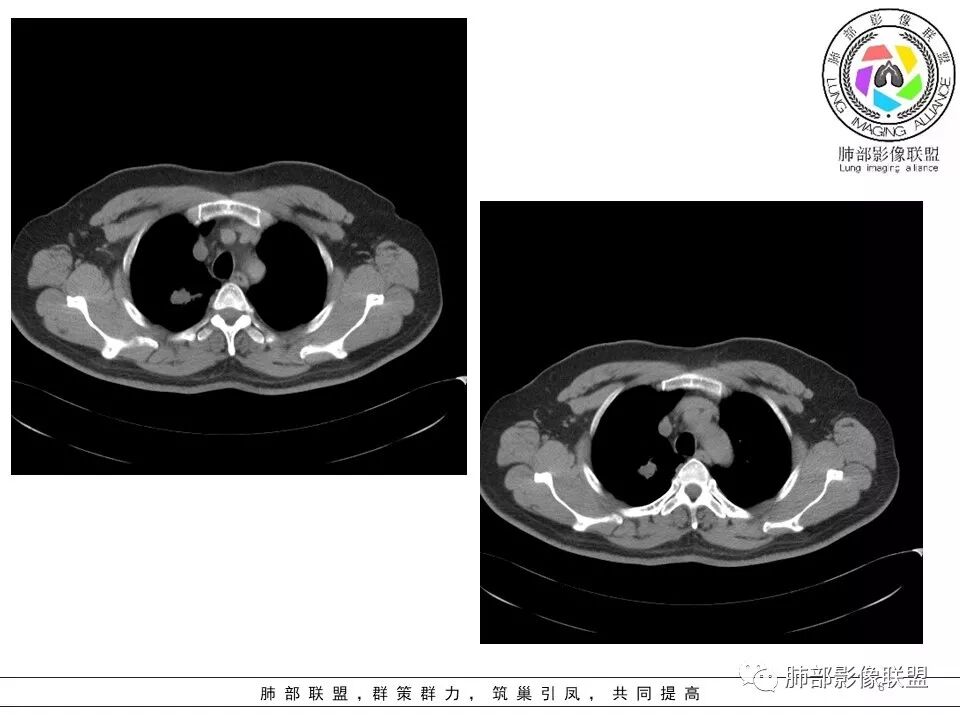

病史:男性,49岁,反复咳嗽月余,伴左胸痛;   影像:形态奇特,长毛刺,疑多灶,支气管阻塞不明显,毛刺不明显,纵膈窗密度不均,其内似见低密度,有凹陷,膨隆不除外,纵膈窗胸膜有点增厚。诊断:结核(右上肺)鉴别:不符合,无钙化,无胸腔积液;腺癌(无淋巴结)。处置:寻找结核相关检查,肿标,纤支镜,增强。

患者中年男性,主诉:咳嗽  胸痛。  胸CT:右肺上叶尖段占位,病灶位于支气管外,病灶周围部分区域可见毛玻璃影,病灶边缘不规则,部分区域可见平直,胸膜牵拉(无胸膜凹陷),柔软长毛刺,分叶,纵隔窗病灶没可见低密度区,左肺尖可见一点状病灶,病灶整体考虑良性疾病:感染性病变(结核?),感染后机化?。恶性病变待除外。

右肺上叶结节,边缘平直为主,病灶比较散,周周似乎有卫星病灶,边缘有胸膜牵拉,从粗到细,左肺尖奕有卫星灶,综合考虑结核。

晨读:患者中年男性,反复咳嗽1月余,伴左胸部疼痛1周就诊。胸部CT:右肺上叶尖后段不规则结节,见长毛刺、胸膜牵拉、条索影,周围见卫星灶。未见明显淋巴结肿大,符合结核病变。鉴别其他。但其病灶位于右肺,主诉左胸痛,是误写,还是?

一米阳光:    晨读,右上肺结节影,形态不规则,边缘平直,部分凹陷,长软毛刺,胸膜牵拉,周围卫星灶。考虑结核。鉴别腺癌,部分边缘彭隆

傅昌瑜:  男,49岁,反复咳嗽1月余,伴左侧胸痛1周。右肺上叶尖段结节,边缘平直、凹陷,周周似乎有卫星病灶,边缘有胸膜牵拉,从粗到细,左肺尖见小点状病灶,考虑良性病变,结核可能性大。

灵魂清零: 右上肺结节影既有良性征象也有恶性征象,良性:边界平直,形态扁平,左肺尖有病灶;恶性:周围边界清楚的磨玻璃影,内部密度不均匀,局部边界有膨隆!考虑腺癌,肉芽肿病变待排!进一步增强扫描!再穿刺活检检查!

小飞:  晨读:右肺上叶不规则结节灶,沿支气管走形分布,边缘平直,U型凹陷,脊柱侧有少许磨玻璃影,左肺尖少许斑点灶,综合考虑结核。

丽:  右上肺结节,有平直征、U形征,部分边缘呈膨隆,倾向于良性病变,考虑肉芽肿性病变可能。